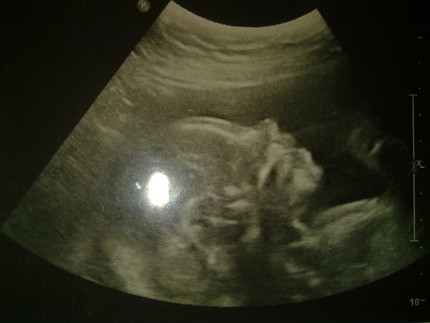

Беременность 22 недели мальчик

Беременность 22 недели мальчик 115 фото